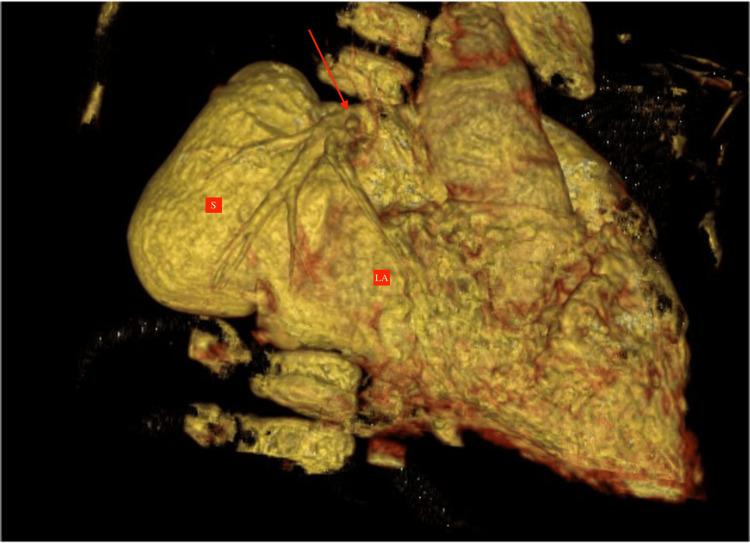

The pulmonary artery-to-left atrium (LA) fistula is one of the rare and unique structural causes of silent cyanosis. This correctable abnormality can be identified by having a high index of clinical suspicion and appropriate investigations using echocardiography and cardiac computed tomography (CT). We report an eight-year-old child who had worsening exertional dyspnea, long-standing central cyanosis, and recurrent infections. A large-sized fistula connecting the right pulmonary artery (RPA) to the LA with all the right- and left-sided pulmonary veins showed normal drainage into the LA, suggesting a type I RPA-to-LA fistula, which was diagnosed on cardiac CT. Percutaneous closure using the occluder device is planned as further management for the patient.

肺动脉至左心房瘘是导致隐匿性发绀的罕见且独特的结构性病因之一。这种可纠正的异常情况可通过高度的临床怀疑指数以及使用超声心动图和心脏计算机断层扫描(CT)进行适当检查来识别。我们报告一名8岁儿童,其劳力性呼吸困难加重、长期中心性发绀且反复感染。一个连接右肺动脉(RPA)与左心房的大型瘘管,所有左右肺静脉均正常引流至左心房,提示为I型RPA至左心房瘘,这是通过心脏CT诊断出来的。计划使用封堵器进行经皮封堵作为该患者的进一步治疗措施。